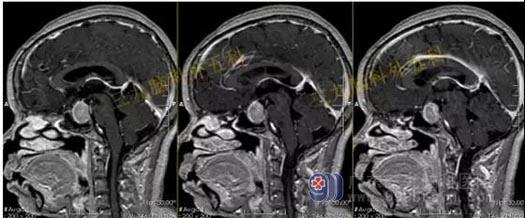

术前头部MR检查结果:鞍区示一团块状占位性病变,T1WI呈略低信号,T2WI呈稍高信号,增强后呈明显强化,病变界限清晰,边缘光整,范围约为3.1cm×2.7cm×2.0cm。病变示明显束腰征,垂体柄及视交叉受压显示不清,邻近颈内动脉受压移位,部分被包绕。

结果:鞍区垂体大腺瘤;病变部分包绕邻近颈内动脉。

手术过程:内镜下经鼻蝶鞍区垂体大腺瘤切除术,术中磨除鞍底,先行瘤内减压,双吸引器有序切除肿瘤,垂体及鞍隔保护良好,无脑脊液漏形成,肿瘤全切。

术后头部MR检查提示:肿瘤已全切。